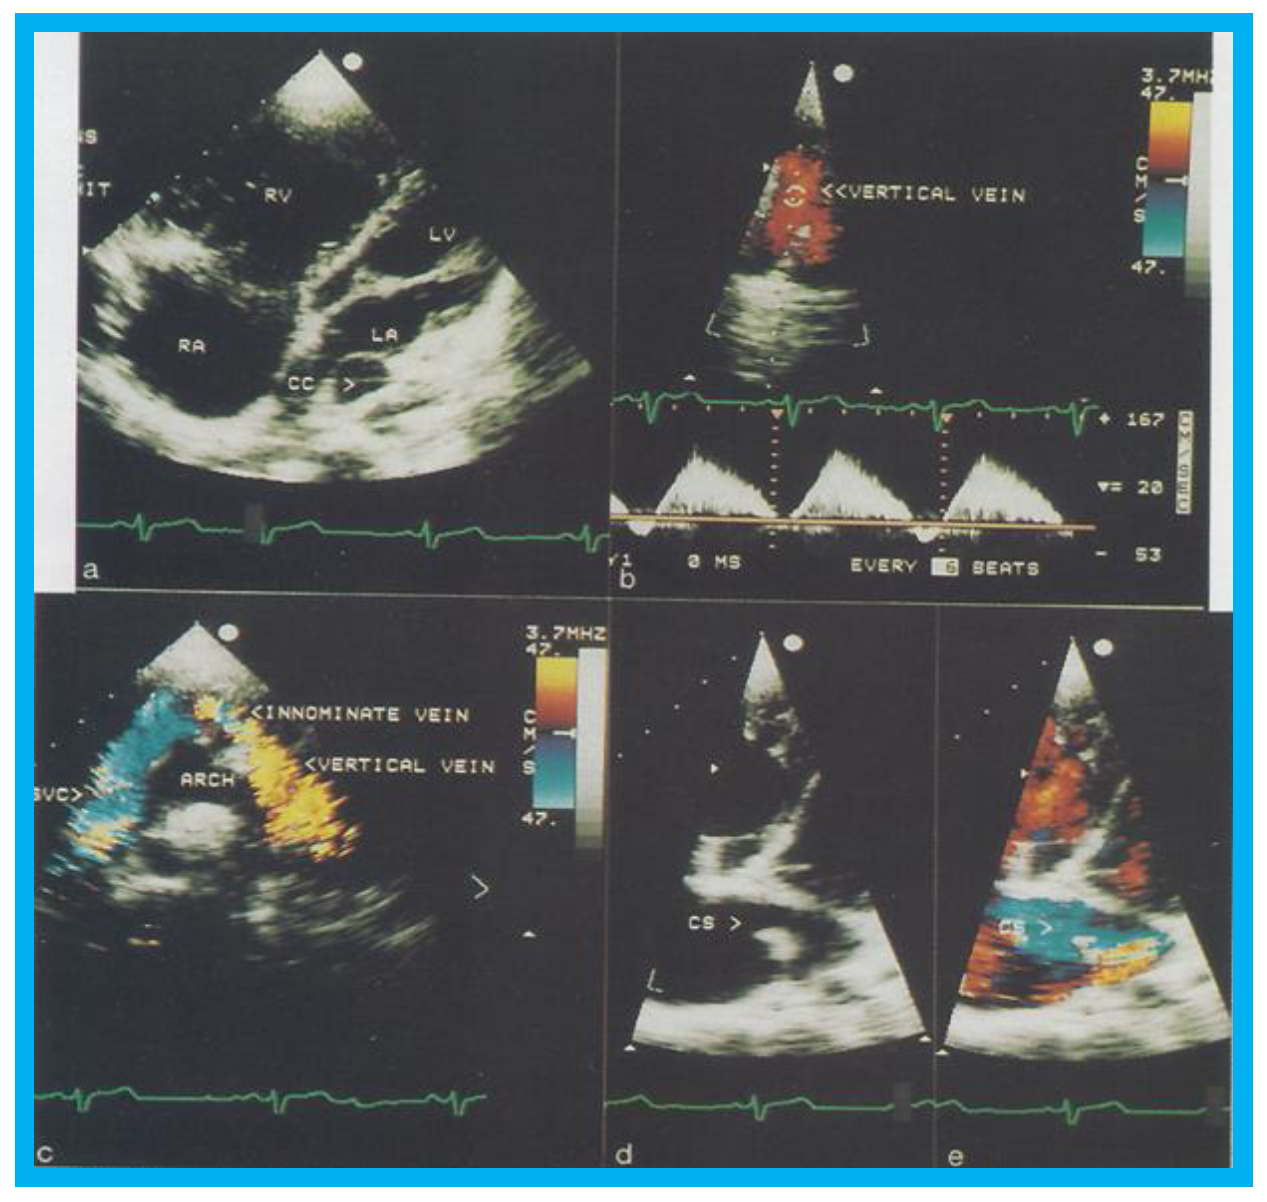

Transthoracic echocardiogram in case 1 showed dilated right atrium (RA) and right ventricle (RV) with a common pulmonary venous confluence (Figure 6a) and a vertical vein emptying into the innominate vein and superior vena cava (SVC) (Figure 6b,c). Dilated coronary sinus (CS) with mosaic color-Doppler flow pattern of pulmonary venous entry was also seen (Figure 6d,e). These findings indicated mixed type of total anomalous pulmonary venous connection. The findings in case 2 were very similar to those seen in case 1. However, not all pulmonary veins were identified and their course and connections to the pulmonary venous confluence could not be established. Therefore, catheterization and cineangiography were undertaken to validate the diagnosis prior to corrective cardiac surgery. Levo-angiographic frames following right pulmonary artery cineangiogram demonstrated entry of right pulmonary veins into the coronary sinus in both cases (Figure 7a,b,d). Direct injection into the left pulmonary vein via a catheter positioned into it via the innominate and vertical veins in the first case (Figure 7c) and on levo-angiogram following left pulmonary artery cineangiogram in the second case (Figure 7e) clearly demonstrated left pulmonary venous drainage via the vertical vein into the systemic venous circuit. Transesophageal echocardiography during surgery in both cases could not delineate the number of pulmonary veins and their connection with the confluence, although we had only access to single-plane TEE probe at that time.

Figure 6. Selected two-dimensional (a) and color flow images (be) of a patient (case 1) with mixed type of total anomalous pulmonary venous connection are shown. In (a), dilated right atrium (RA) and right ventricle (RV) and common pulmonary venous confluence (CC) are illustrated. In (b,c), spectral and color flow images demonstrate the vertical vein draining into the innominate vein and superior vena cava (SVC). In (d,e), dilated coronary sinus (CS) with mosaic color flow pattern of pulmonary venous entry are apparent. ARCH, aortic arch; LA, left atrium; LV, left ventricle. Reproduced from Reddy S.C.B., et al. [8].